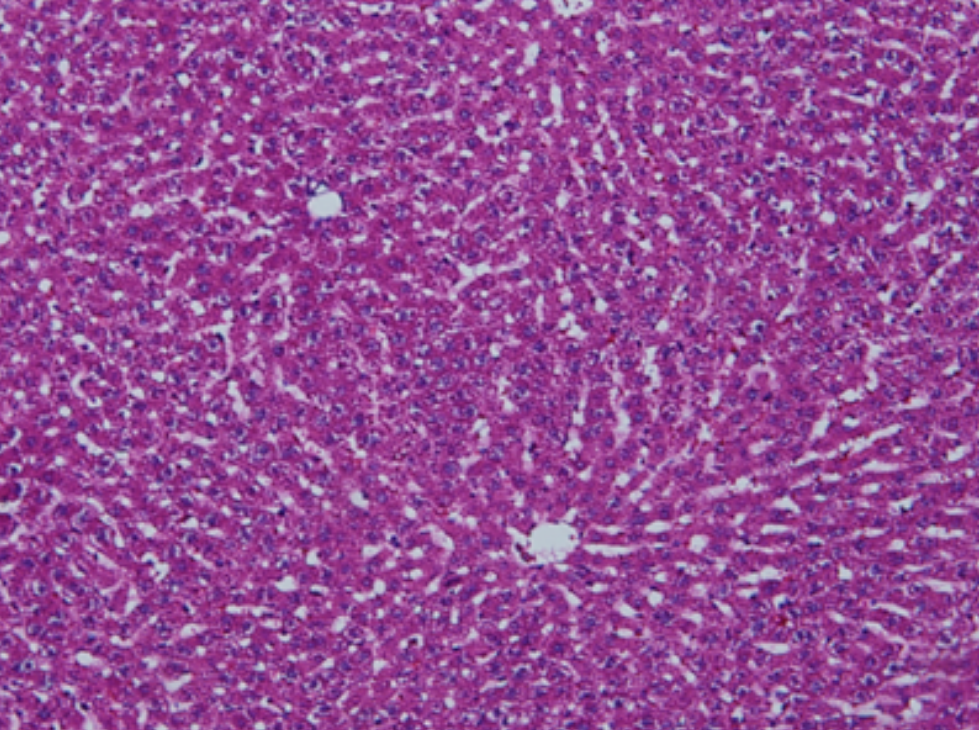

HE染色,全称苏木精-伊红染色法(Hematoxylin and Eosin staining),是最常见的组织切片染色技术之一,用于在显微镜下观察和分析组织或细胞的结构和形态。虽然HE染色是最常见且最基础的染色技术之一,😭但在实验过···

HE染色,全称苏木精-伊红染色法(Hematoxylin and Eosin staining),是最常见的组织切片染色技术之一,用于在显微镜下观察和分析组织或细胞的结构和形态。

虽然HE染色是最常见且最基础的染色技术之一,😭但在实验过程中,很容易出现各种情况导致染色切片质量参差不齐。所以,小编根据以往实验经验,给大家整理归纳出了15个HE染色中的常见问题,还包含问题原因分析以及解决方法哦~